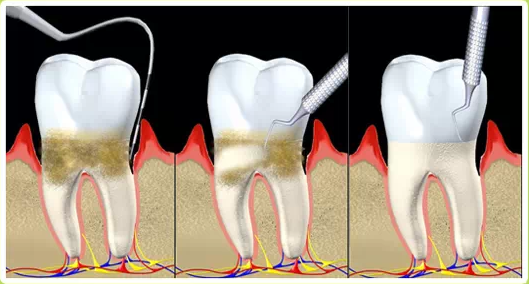

牙周炎發(fā)展到一定階段時(shí),僅采用基礎(chǔ)治療難以取得較好療效,必須通過(guò)適時(shí)而合宜的手術(shù)治療挽救患牙,才能保持牙周組織健康,延長(zhǎng)患牙在口腔內(nèi)的壽命,維持牙列的完整性,促進(jìn)全身健康。其手段包括齦下刮治、根面平整、牙周翻瓣術(shù)、牙齦切除術(shù)、牙周夾板固定術(shù)等。